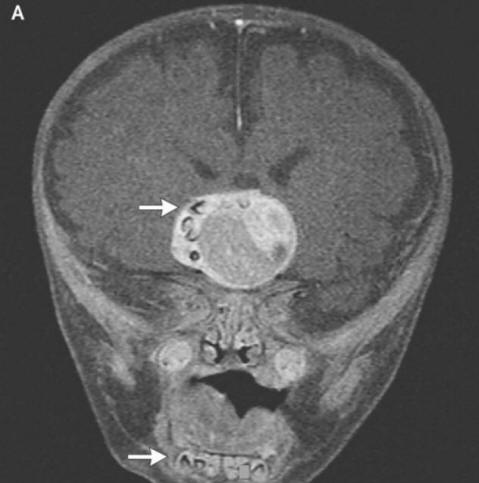

Kirurgi iz ameriške zvezne države Maryland so ga morali preživeti najtežjih operacij v svoji praksi. Štirimesečni starši fantje so sprožili alarm in po njem odšli k zdravnikom opazili, da glava njihovega otroka prehitro raste. Zdravniki opravili pregled in ugotovili, da je zob zrasel v bolnikovih možganih.

Fotografija iz odprtih virov Kot so razlagali kirurgi prestrašenim staršem in onkologi so bili to posledica nastanka redkega prirojenega tumorjev – kraniofariniomov, piše New England Journal of Medicine. Ta neoplazma v veliki večini primerov benigna pa lahko zraste do velikosti kroglice za golf in povzroča zmanjšanje vonja, poslabšanje sluha in vida ter povečuje tudi intrakranialni tlak. Raziskovalci vedno sumili, da se ti tumorji, ki se pojavijo pri otroku že prej nosečnost, ki nastane iz istih celic kot zob, saj so zaznali velike kopičenja kalcija, vendar pravi oblikovan zob, preden tega primera ne najdejo obračunano.

Kirurgi so fotografijo uspešno odstranili iz odprtih virov. Tumor oz. fant, so rekli, gre dobro. Vendar zob, ki odraščal v njegovi hipofizi, vendar je motil zlasti možgane, pravilna proizvodnja hormonov – bolnik jih bo moral vzeti prej konec življenja. Ta primer lahko upravičeno prevzame svoje mesto seznam najčudnejših operacij, ki jih opravijo onkologi. Medtem pa v mladenič iz Irana, ki je moral zdravite poraščene oči. Skoraj se je pojavil čuden tumor v očesu takoj po rojstvu, vendar se je pri 19 letih znatno povečala v velikosti (do 0,6 cm) in poleg tega preprečili zapiranje vek strogi lasje so začeli rasti. Zdravniki so tumor odstranili in to ugotovili gre za limbalni dermoid – navadno izjemno redko benigna vzgoja. Po mnenju zdravnikov bi v tem primeru dr. če bi mladenič še naprej vlekel z zdravili, je njegova oteklina ni mogel samo rasti las, ampak tudi začeti znojiti: sčasoma na novotvorbah se pogosto pojavijo ustrezne žleze.